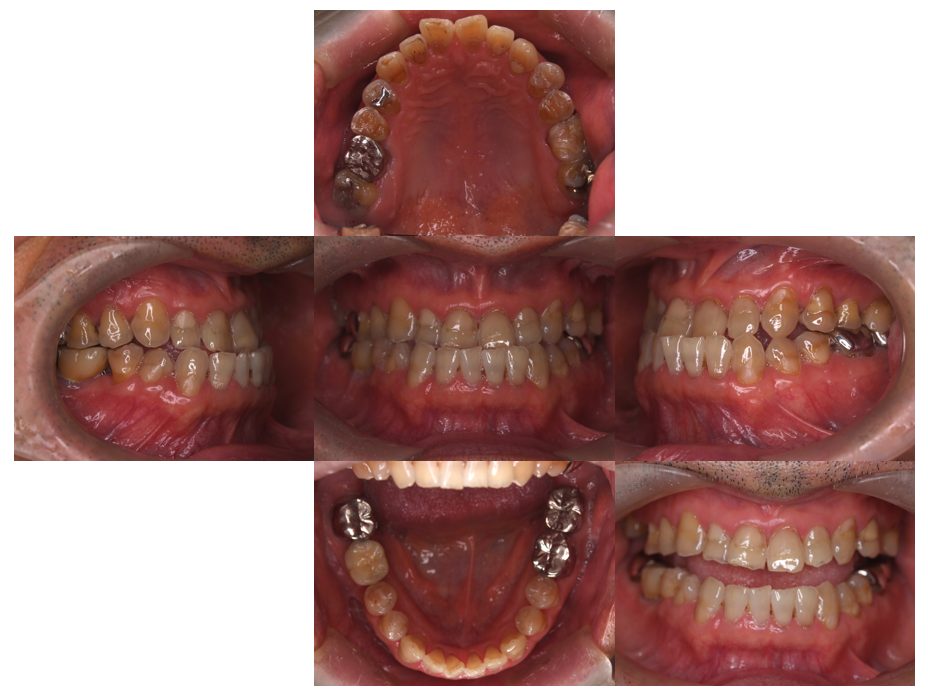

| 主訴 | 60代女性 他院で義歯を作ったが噛みにくい、バネを掛けている左下の銀歯が何度も取れる、しっかり噛めるようになりたい |

| 治療内容 | 歯周病組織再生療法、インプラント治療、セラミック治療を行いました。 |

| 治療費 | 4,000,000円(税込み) |

| 治療期間 | 1年半 |

| 治療回数 | 25回 |

| 想定されたリスク | 失活歯が多く、太くて長い土台がすでに入っていたので、歯根破折のリスクがあった |